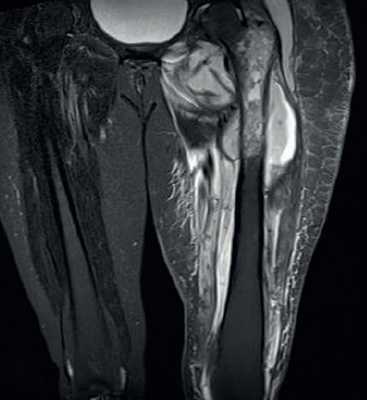

МРТ Т2-взвешенного типа. Остеомиелит большеберцовой кости. Яркий сигнал соответствует костной деструкции и распространению по костному мозгу.

МРТ бедренной области. Остеомиелит бедренной кости с поражением мягких тканей с формированием абсцесса.